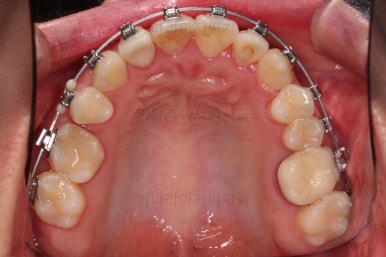

적절하게 디테일을 손보고 마무리를 합니다.

중간중간 보철된 치아도 있고, 위아래의 중앙선까지 100% 맞기는 힘든 상황이었지만 가급적이면 매우 잘 맞춰 드렸고요.

교합이라던지 가지런한 느낌도 좋네요.

우측만 위아래 뽑았지만 기능에는 문제 없이 교합을 마무리 했습니다.